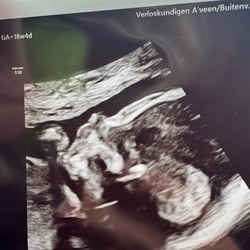

Vandaag deze bij de ikea gehaald

Deze